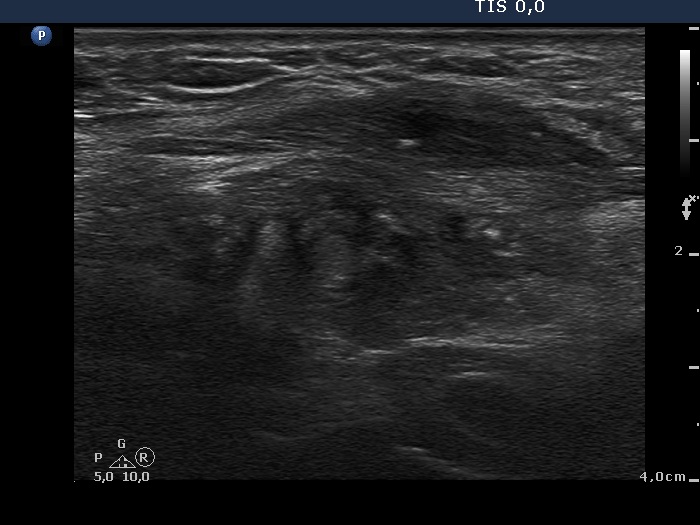

Six months after surgery (second row of images):

Clinical data: The patient had no complaints.

Palpation: no abnormality.

Result of blood tests: euthyroidism (TSH 3,08 mIU/L).

Ultrasonography. The presentation of the right lobe was unchanged. The left lobe was minimally hypoechogenic and contained a hypoechogenic area with irregular shape. In contrast with the former examination, the operated left lobe became well-demarcated.

Comment. Considering the postoperative presentation of the left lobe, the type of surgery appears to be subtotal rather than near total.